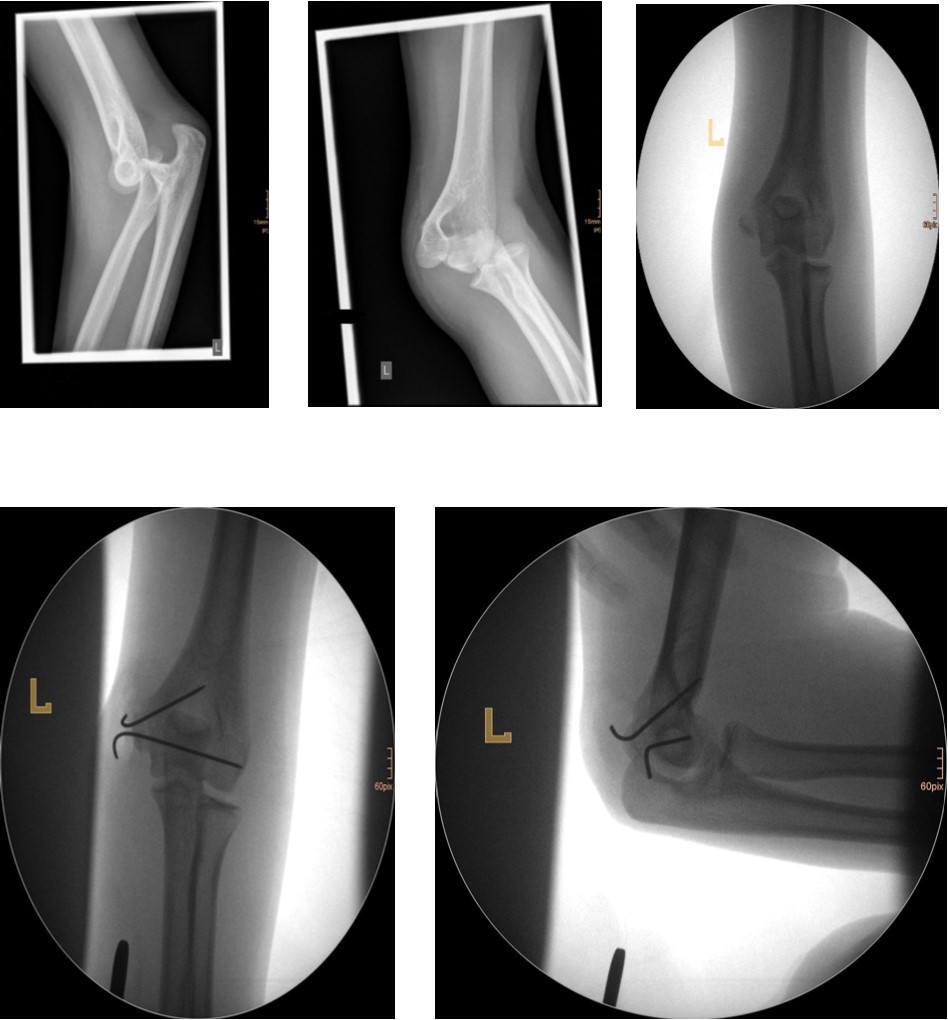

The fracture fragment can be approached by a posteromedial incision that allows good exposure of both the fracture site and the ulnar nerve. Fixation is easily achieved with smooth K-wires or with screws in older adolescents. Two wires are necessary because of the sagittal rotation forces exerted on the fracture fragment by the common flexor muscles. Figure 4 and Figure 5.

Figure 4.14 year old female patient with a elbow dislocation and a dislocated left epicondyle fracture which was treated by open reduction and osteosynthesis with two divergent Kirschner wires (personal collection)